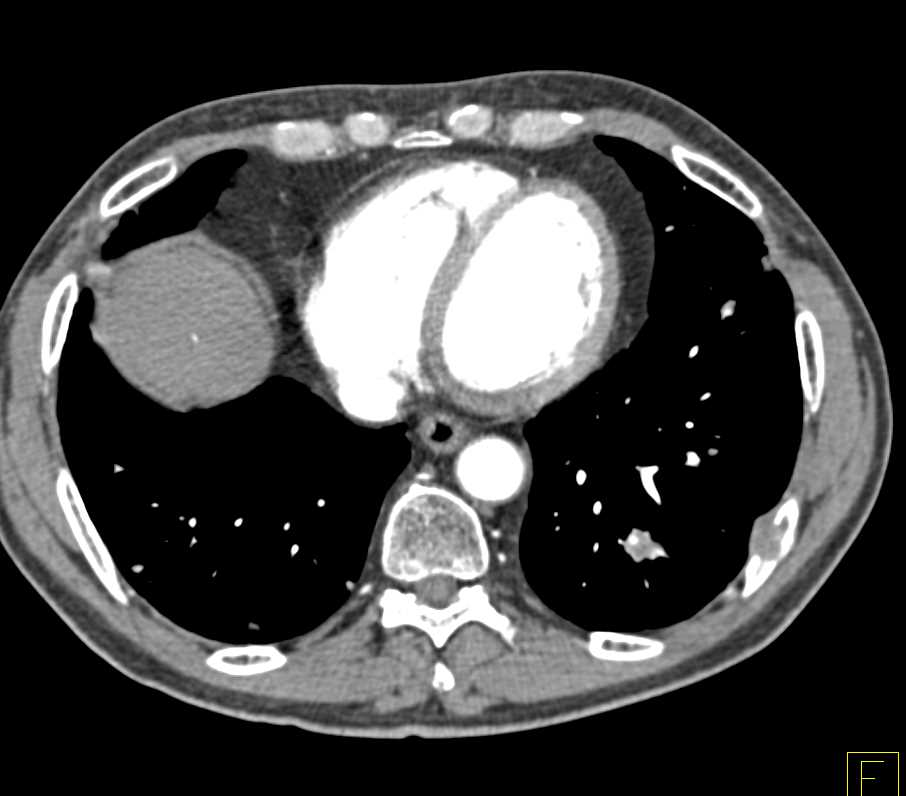

Diagnosis

Metastatic Renal Cell Carcinoma to the Brain